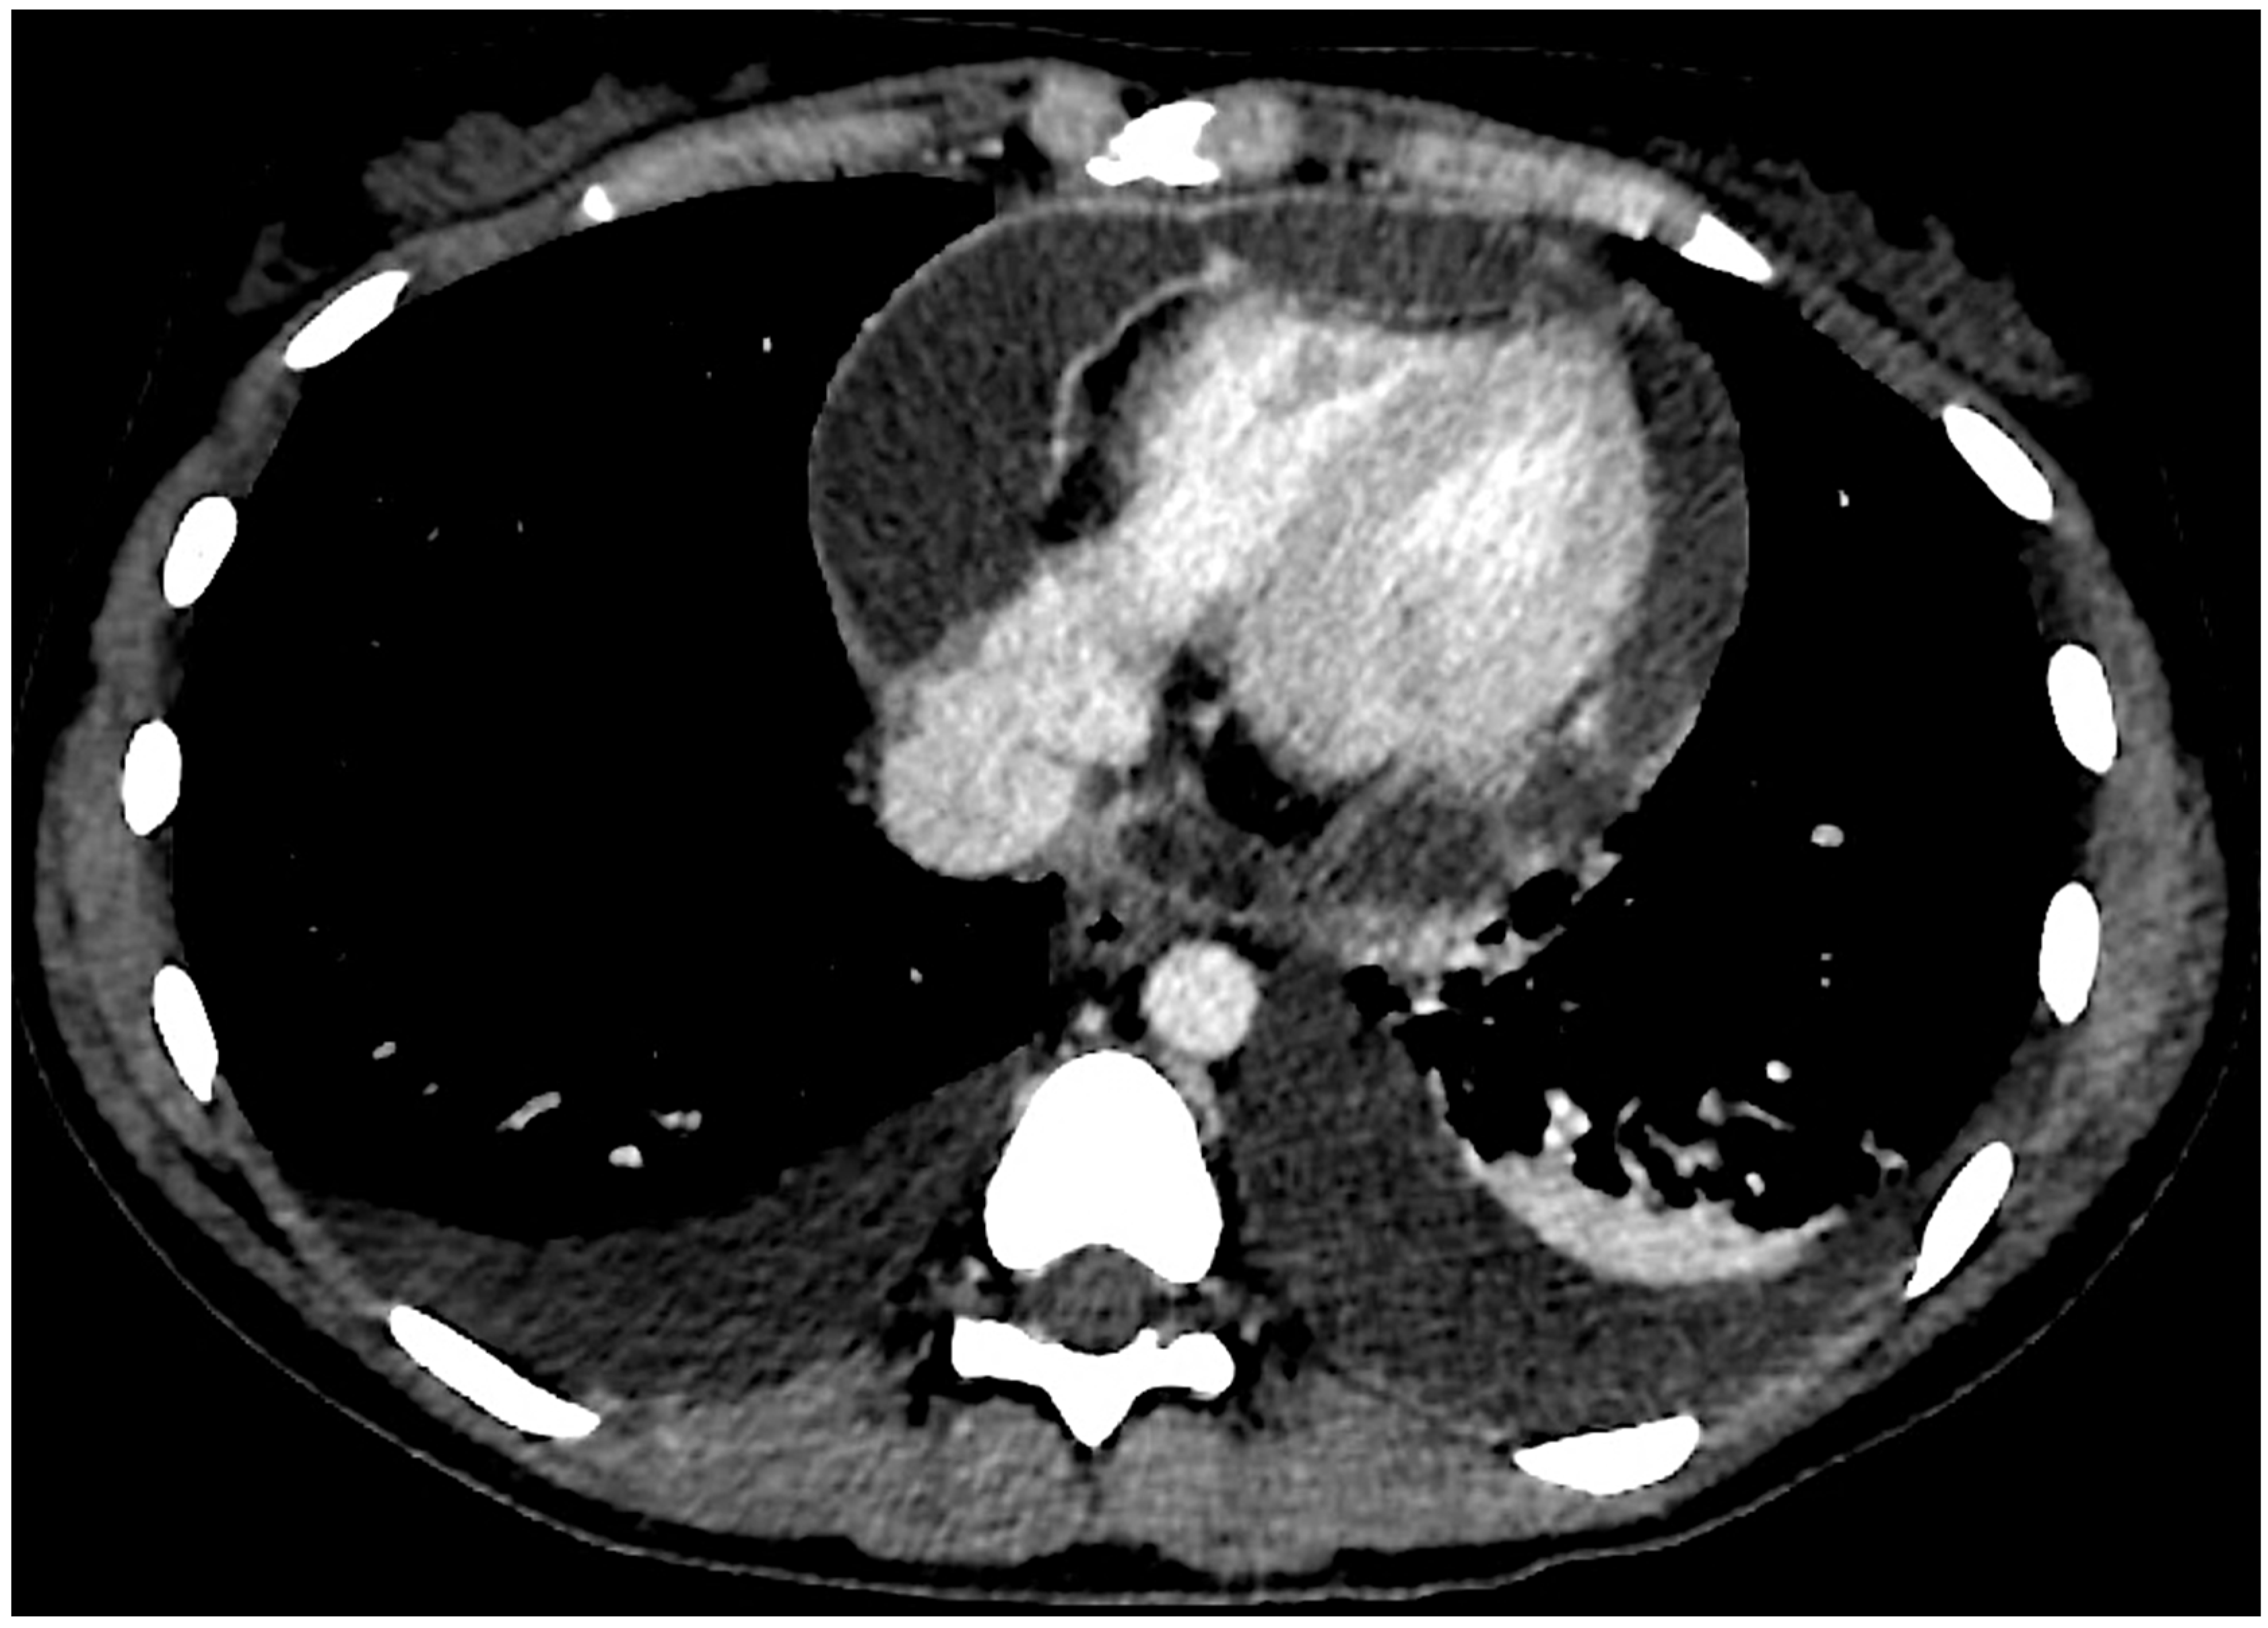

2.2. Current Assessment and Differential Diagnosis